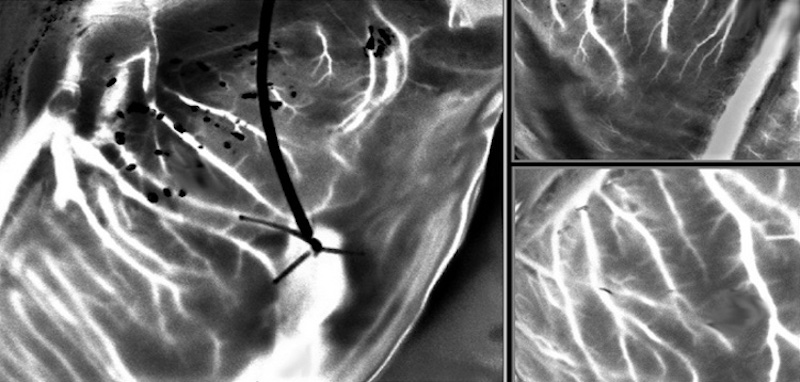

A powerful tool for imaging donor hearts, laser speckle captures detailed images of blood vessels in a beating heart outside the body. Credit: Paris-Saclay University.